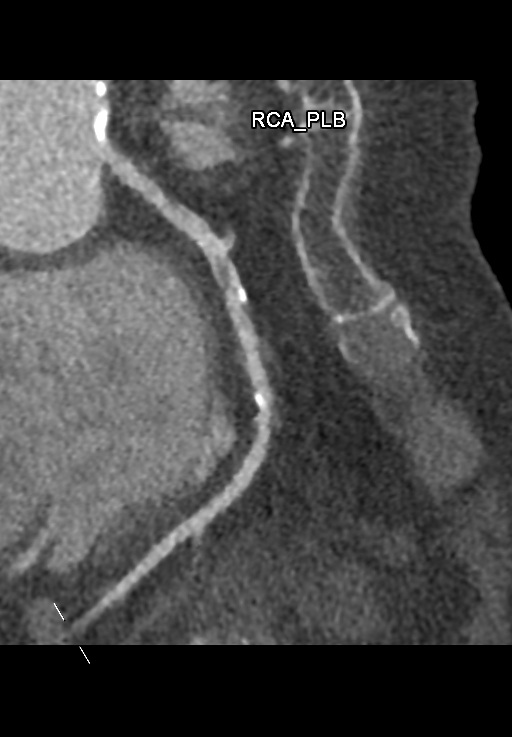

A 78-year-old woman with hypertension, hyperlipidemia, and a history of PCI to the right coronary artery with bare-metal stent placement in 2001 presented with a one-month history of stable angina. She underwent CT coronary angiography, which demonstrated moderate to severe in-stent restenosis in the RCA. She was admitted electively for coronary angiography and possible PCI. Physical examination was unremarkable, with no murmurs or signs of heart failure.

Dominance: Right Left Main: No significant stenosis LAD: Mild distal disease LCx: Minor disease RCA: 80% in-stent restenosis at proximal segment; 80% calcified de novo stenosis at mid to distal RCA

The diagnostic angiogram confirmed significant ISR at the proximal RCA stent, with severe calcification, and a de novo significant stenosis in the mid-distal RCA. The procedure was performed via the right radial artery approach. Initial attempts to engage the RCA with a 6Fr Ikari Left 3.5 guide were unsuccessful. Switching to a 6Fr Judkins Right 4 guide provided suboptimal support, necessitating the use of a Guidezilla II guide extension catheter. The posterior descending artery (PDA) was wired with a Sion Blue wire. Intravascular ultrasound (IVUS) confirmed severe calcification within the ISR segment. Predilatation of the distal RCA lesion and proximal RCA ISR with an Aperta NSE 3.0/13 balloon resulted in poor balloon expansion. Intravascular lithotripsy (IVL) was performed using a 3.0/12Shockwave balloon, delivering 100 cycles to both lesions. Post-IVL IVUS demonstrated adequate lesion preparation. The distal RCA lesion was stented with an Ultimaster Nagomi 3.0/28 mm DES, followed by post-dilation with a non-compliant 3.25/15 mm balloon.The proximal RCA ISR was treated with an Ultimaster Nagomi 3.5/33 mm DES, post-dilated with a non-compliant 3.5/15 mm balloon up to 22atm. Final IVUS confirmed good stent expansion and apposition, with no edge dissection. The final angiogram demonstrated a satisfactory result with TIMI 3 flow.